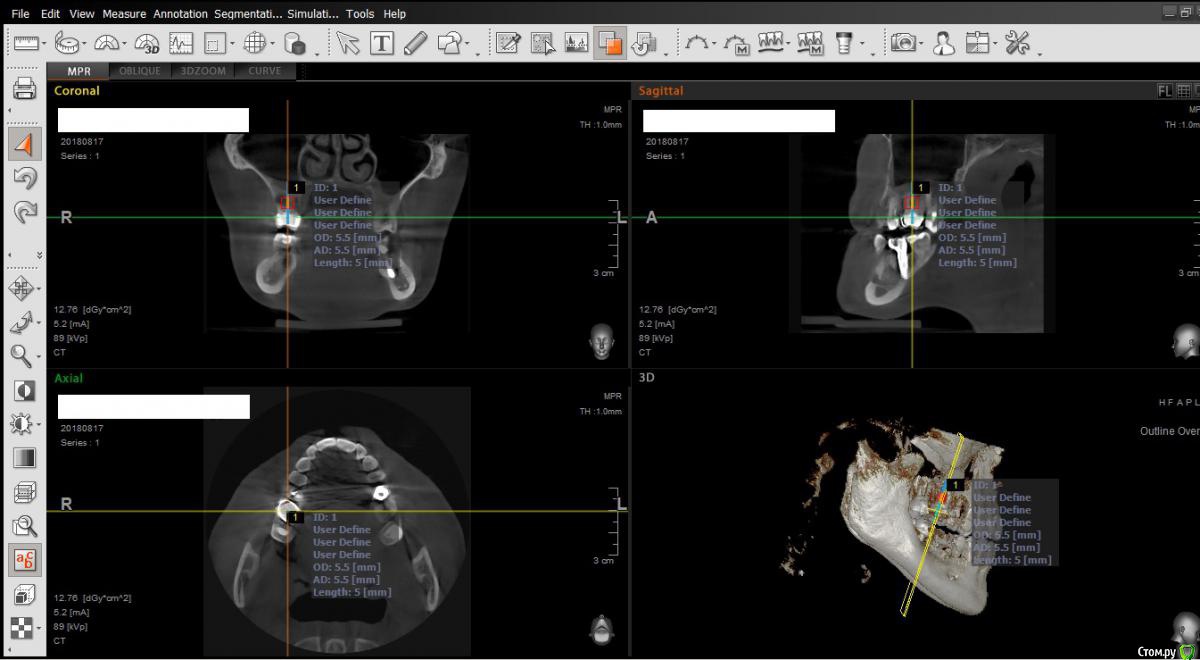

alex_www1 Опубликовано 10 декабря, 2018 Поделиться Опубликовано 10 декабря, 2018 Добрый времени суток!У меня супруга собирается делать имплант, верхняя шестерка, её врач ей сказал делать только с синус лифтингом т.к. близко гайморова пазуха, около 6мм, супруга раньше страдала гайморитом очень нудно и долго, потом оно как-то утихло но воспоминания остались, поэтому супруга боится данной процедуры, боится возвращения старых проблем. Я стал читать и нашел что есть импланты эниридж ширины 5.5мм на 5мм высоты. Позвонила супруга врачу на их счет, он сказал их ставить не будет т.к. это только для людей старше 50-60 лет, т.к. недолговечны, ставить не будет даже полностью под ее отвественность(она предложила). Далее я взял программу и "вставил" этот имплант, я конечно не специалист, может что-то не так сделал, но по моему "вошло" хорошо. Если что не так "палками не бейте". Скажите вы также думаете что нельзя поставить такой имплант? Хоть убей не понимаю почему... Приложил фото того что получилось в программе, если куда-то надо "покрутить" скажите, крутану Ссылка на комментарий

alex_www1 Опубликовано 11 декабря, 2018 Автор Поделиться Опубликовано 11 декабря, 2018 как оказалось есть более свежий снимок, от конца августа этого года. и похоже я не на тот зуб "навел", у супруги будут делать правую верхнюю 6ку, а я похоже навел на левую верхнюю. в общем вот более новый снимок. Ссылка на комментарий